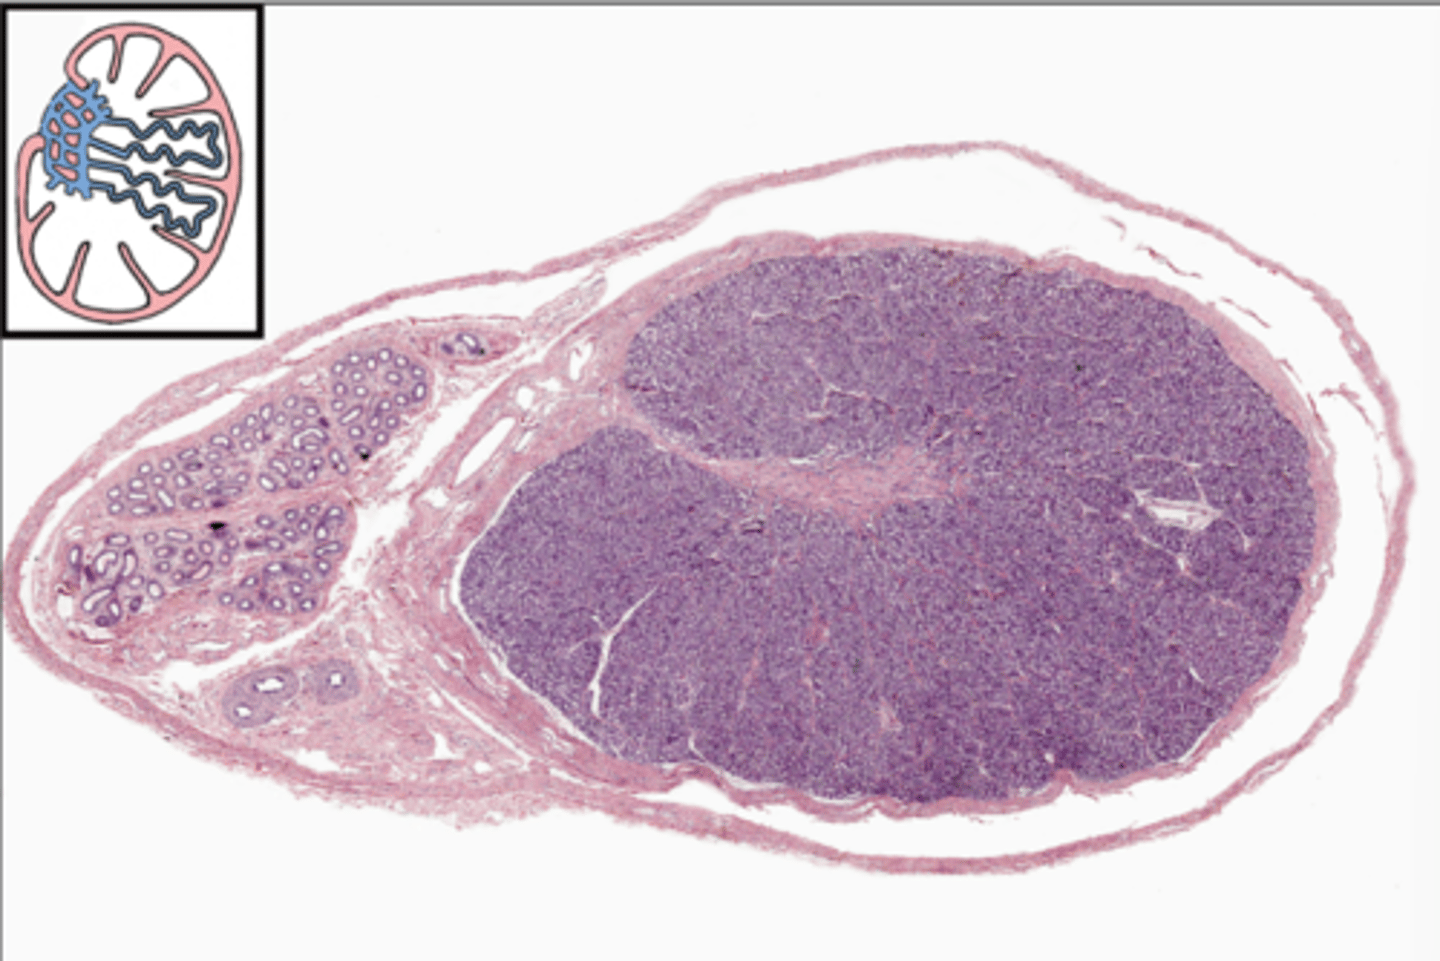

Testis (testes)

Testis (testes)

Testis (testes)

Testis (testes)

Tunica albuginea

Tunica vaginalis

Seminiferous tubules

Seminiferous tubules

Seminiferous tubules

Leydig cell

Leydig cell

Lobule

Septum

Rete testis

Efferent ductule

Epididymis